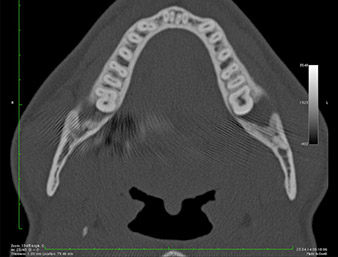

Nell'immagine 3D (tomografia volumetrica digitale) era visibile che il residuo di radice era collocato in posizione distocaudale nella transizione dalla porzione orizzontale alla porzione ascendente della mandibola (Fig. 2).

In base all'anamnesi, il paziente (non fumatore, 26 anni) presentava probabilità molto elevate di un outcome positivo. A causa dell'indicazione della stretta vicinanza del residuo di radice al nervo alveolare inferiore nella radiografia panoramica, è stata utilizzata anche la tomografia volumetrica digitale (6).